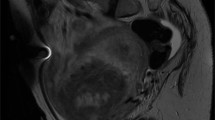

The term AUS is a descriptive diagnosis, recommended when cytologic atypia is present, but it is difficult to opine if this is inflammatory atypia or neoplastic, and to a degree that dysplasia or for that matter CIS cannot be ruled out with certainty, as occurs in a background of inflammation (Fig. 3)1,5,22. As mentioned above, some experts prefer merging AUS with dysplasia, although for clarity, dysplasia is a term used when the urothelium has appreciable cytologic and architectural changes that are felt to be preneoplastic, yet they fall short of the diagnostic threshold for urothelial CIS.